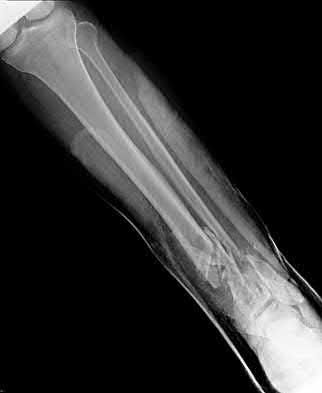

1. # A 32-year-old male sustains the injury shown in Figure A and undergoes treatment as shown in Figure B. Following placement of this implant, what is the best technique to confirm it is not too proud proximally?

1. Lateral radiograph of the knee

2. AP radiograph of the knee

3. Oblique radiographs of the knee

4. Merchant radiograph of the knee

5. Internally rotated 45 degree view of the knee Corrent answer: 1

The safe zone for tibial nail placement as seen on radiographs is just medial to the lateral tibial spine on the anteroposterior radiograph and immediately adjacent and anterior to the articular surface as visualized on the lateral radiograph.

Tornetta et al specifically located the safe zone for nail entry in a study using fresh frozen cadaver knees. The authors found that the safe zone for nail placement is located 9.1+/-5 millimeters lateral to the midline of the plateau and three millimeters lateral to the center of the tibial tubercle. The width of the safe zone averaged 22.9 millimeters and was as narrow as 12.6 millimeters.

The starting point of the of the nail can be best viewed on the lateral knee radiograph, an example of which is shown in Illustration A. Illustration B shows the "sweet spot" for nail insertion as defined by Tornetta.